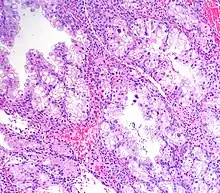

Micrograph showing Arias-Stella reaction in endometrium

Arias-Stella reaction, also Arias-Stella phenomenon, is a benign change in the endometrium associated with the presence of chorionic tissue.[1]

Arias-Stella reaction is due to progesterone primarily. Cytologically, it looks like a malignancy and, historically, it was diagnosed as endometrial cancer.[1]

It is characterized by nuclear enlargement and may also have any of the following: an irregular nuclear membrane, granular chromatin, centronuclear vacuolization, and pseudonuclear inclusions.[1]